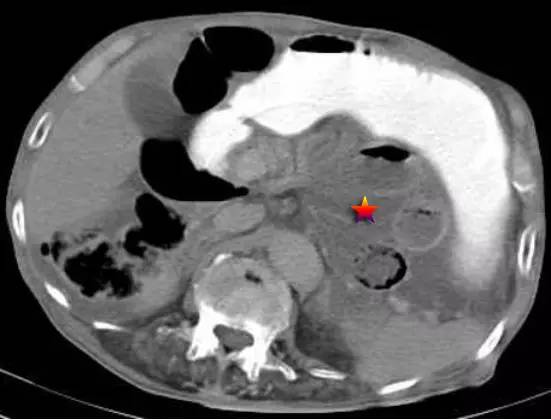

下图为左侧十二指肠旁疝(☆),疝囊指向左侧,系膜及血管被牵扯至左侧,开口向右。